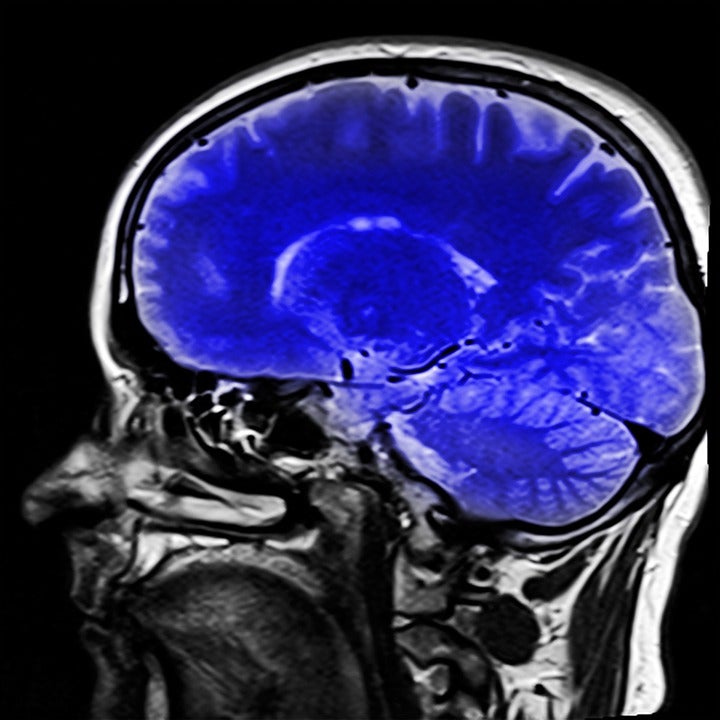

Las imágenes por resonancia magnética, una vía prometedora para predecir la demencia

Una investigación realizada en la Escuela de Medicina de la Universidad de Washington y en la Universidad de California, ambas en Estados Unidos, ha revelado que las imágenes por resonancia magnética pueden ser una vía prometedora para predecir la demencia en personas mayores. De hecho, un pequeño estudio predijo con un 89% de precisión quién desarrollaría demencia en tres años.

Sin embargo, las exploraciones cerebrales por resonancia magnética están ampliamente disponibles y permiten a los médicos vislumbrar lo que sucede dentro del cerebro de una persona. Raji y sus colegas de la Facultad de Medicina, entre ellos Tammie Benzinger, profesora de radiología; Parinaz Massoumzadeh y Adedamola Adedokun, y el radiólogo Pratik Mukherjee, de la Universidad de California en San Francisco, analizaron imágenes de resonancia magnética para detectar signos físicos de deterioro cognitivo inminente.

Utilizaron una técnica llamada imágenes de tensor de difusión para evaluar la salud de la sustancia blanca del cerebro, que abarca los 'cables' que permiten que diferentes partes del cerebro se comuniquen entre sí.

"La imagen del tensor de difusión es una forma de medir el movimiento de las moléculas de agua a lo largo de los tractos de la materia blanca --explica Raji--. Si las moléculas de agua no se mueven normalmente sugiere un daño subyacente a los tractos blancos que pueden indicar problemas de cognición".